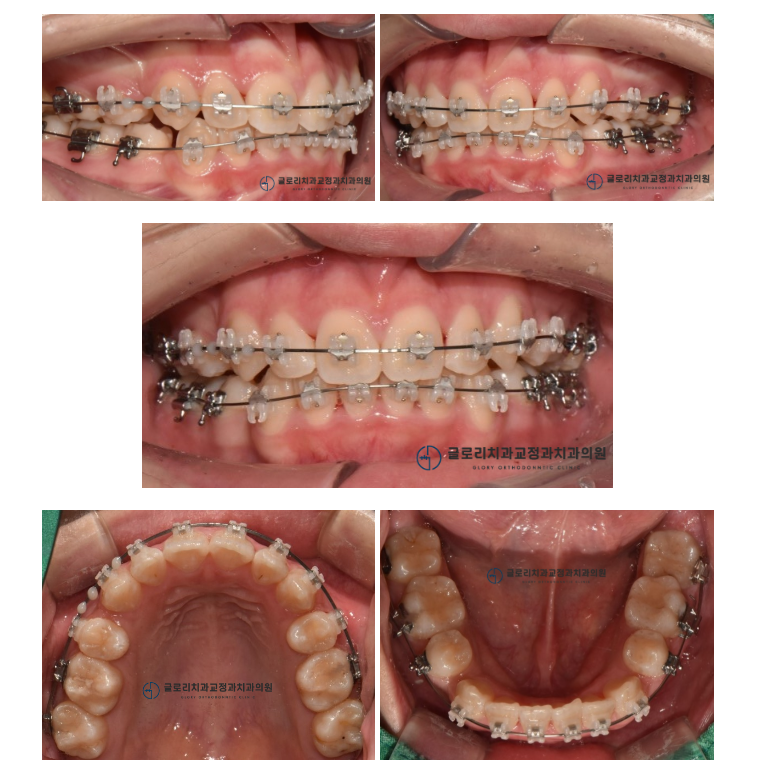

1) 정면

한눈에 봐도 삐뚠 치열을 갖고 있었습니다.

양쪽 송곳니는 정상 배열보다 위로 올라가 있었으며

여기저기 겹쳐있는 치열이 관찰됩니다.

2) 측면

구치부 쪽을 살펴보면 들쑥날쑥한 치열과 더불어

환자께서 말씀하셨던 문제를 확인할 수 있었는데요.

왼쪽 아래 대구치가 쓰러져있었습니다.

또한 # 12 와 # 22를 보면

위,아래가 거꾸로 물리는 반대교합(crossbite)이

나타난 것을 확인할 수 있었습니다.

3) 교합면

악궁 형태도 심하게 찌끄러져 있네요.

쓰러진 곳도 사진에서 보니

더 확연하게 드러나있었는데요.

배열 공간이 모자라서 여기저기 겹쳐 있는

치아들을 확인할 수 있었습니다.

▶ 위 내용을 종합해서 살펴보았을 때,

모자란 공간으로 인해

전체적으로 심한 총생(crowding)이 관찰되었으며

쓰러진 어금니가 관찰되고 있었습니다.

결과

드디어 망우동 치과 의 모든 과정이 마무리되었습니다.

자, 과연 어떻게 변했을지 함께 확인해 볼까요?

전과는 달리 삐뚤어져 있었던 치아들이

매끈하게 펴진 것을 확인할 수 있었습니다.

어금니 교합 또한 톱니바퀴의 형태처럼

맞물려 있는 것을 확인할 수 있었는데요.